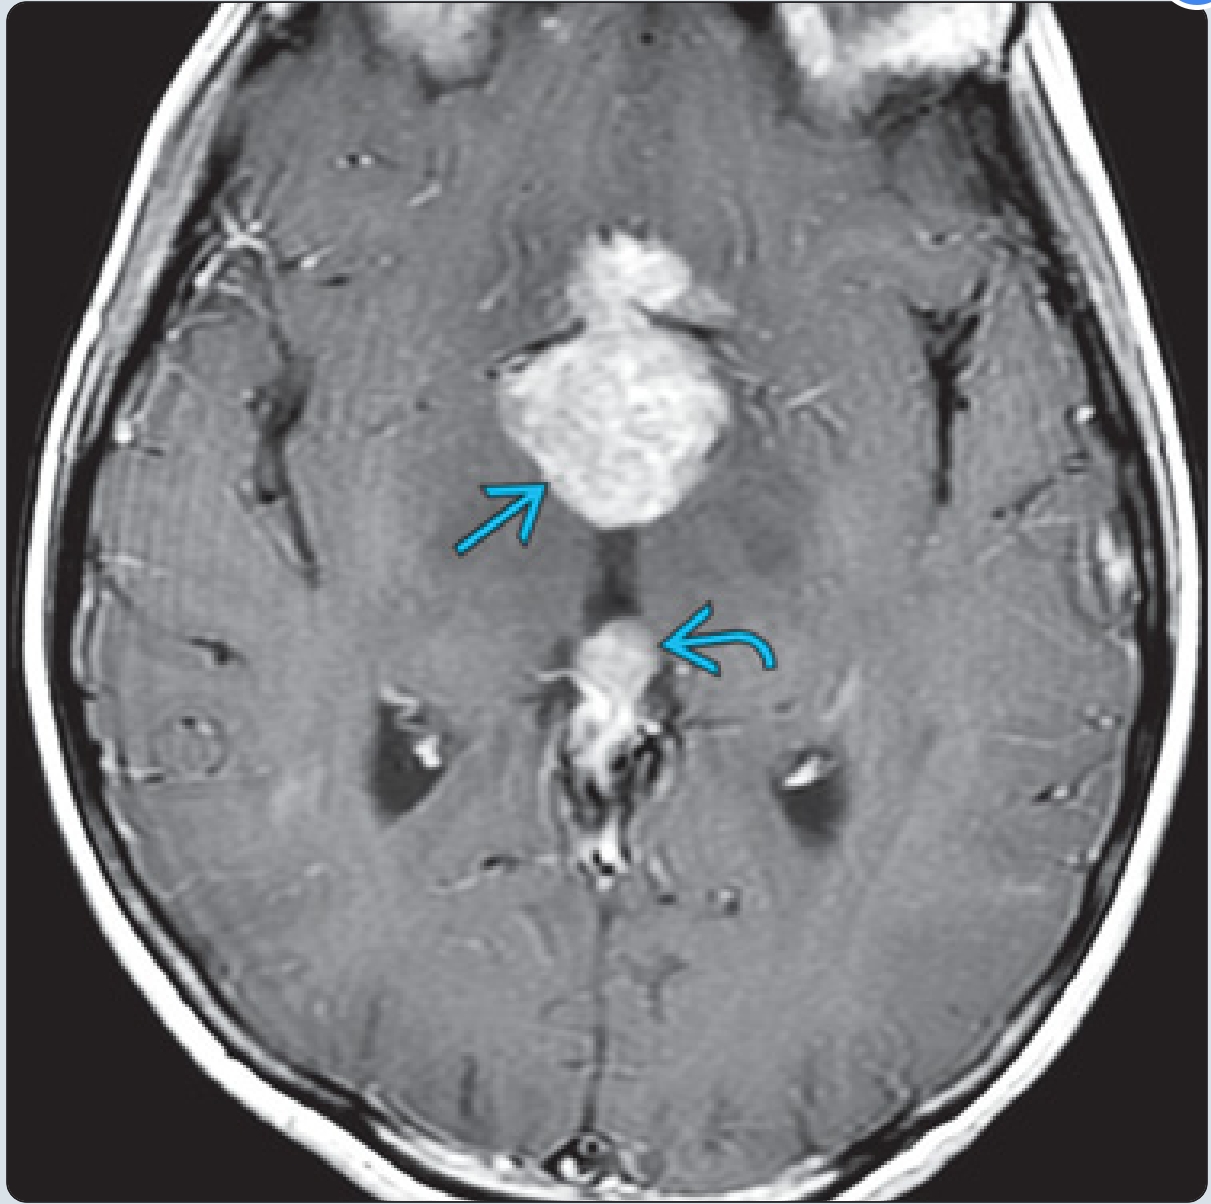

14岁男孩,视力下降,轴位T2WI示鞍上肿块,相对于灰质呈稍低信号。第二个较小的肿块存在于松果体。

同一患者的T1 C+示鞍上病变明显强化。松果体也均匀增大。约20%的病例合并有鞍上和松果体肿块(有时称为“双中线”生殖细胞瘤)